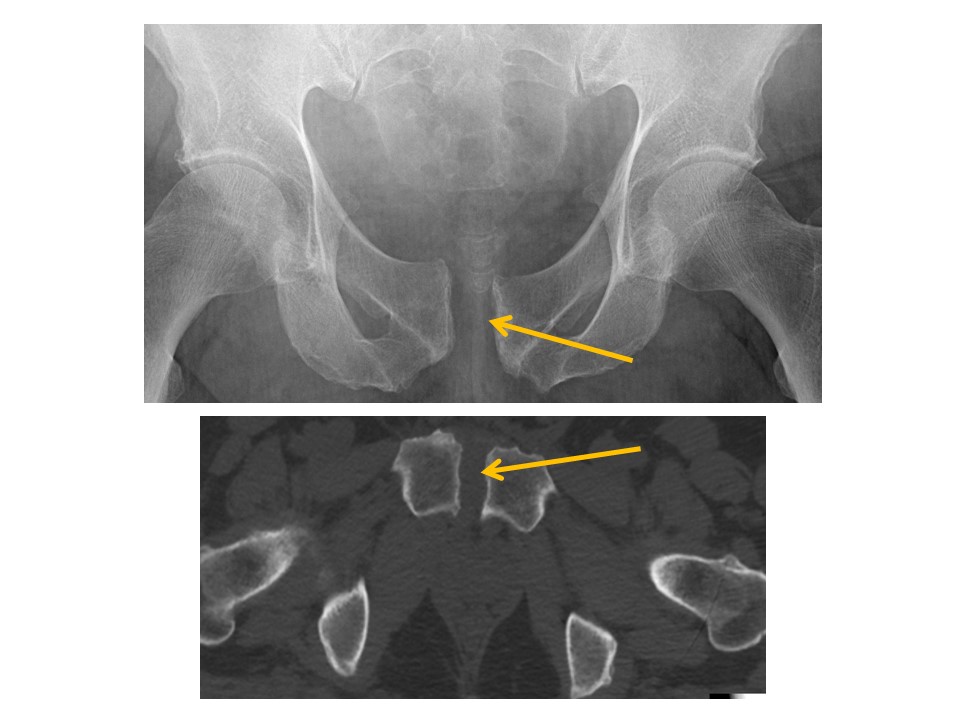

INNOMINATE BONES

There are cortical disruptions or displaced fractures. [Yes/No]

Avulsion fractures are present. [Yes/No]